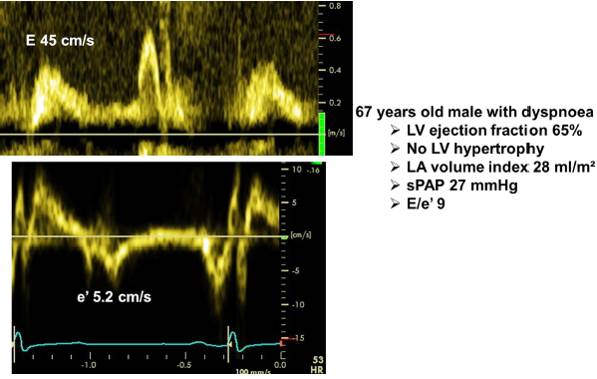

CASE

◆男性,57岁 ,阵发房颤1年余

◆2型糖尿病

◆超声心动图(ECHO)示心房大小正常范围,左室射血分数 60%

◆消融术后第2日夜间患者突发胸闷、憋气、强迫端坐位,咳嗽,咯白色泡沫痰

◆NT-proBNP 由术前155pg/ml升至776pg/ml;

◆动脉血气分析:pH 7.45, pO2:50.6mmHg, pCO2:29.7mmHg;